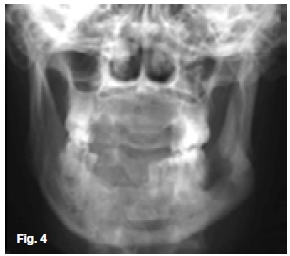

The upper two figures show a case in which there are facial scars of a recurring infection while the pantomo-graph shows ill-defined multilocular radiolucencies with enlargement of the trabecular spaces, suggestive of the presence of a chronic osteomyelitis affecting the hemi-andible on the left side. There are also features demonstrating the formation of sequestra. The case shown in the lower figures started after an assault which had caused a fracture at the angle of the left mandible. A tooth in line of the fracture was removed and since then a draining sinus had developed which showed signs of healing after the removal of sequestrum. In both cases a diagnosis of chronic actionomycotic osteomyelitis of the mandible was made, a rare condition found in 10% of all cervicofacial actinomycosis cases. When it occurs, the radiographic changes are not characteristic. Actionomycosis is a specific infectious disease, primarily caused by the organism Actinomycis Israeli. It affects men twice as frequently as women and is most often encountered in the 20-50 year age groups. The cervicofacial type of actinomycosis is by far the most common, with pulmonary and abdominal actino-mycosis occurring less frequently. However, because of its variable clinical manifestations and difficulty in isolating the causative agent, the diagnosis is often delayed. The actinomycotic infection is not a pure infection; it probably is a result of a synergism between microbes of the ray fungus group and other anaerobic microbes. Clinically, the infection has a prolonged course. The first sign is the appearance of a red to dark blue, nodular infiltration, often located within the skin of the subman-dibular area or angle of the jaw. Untreated, the infection spreads along anatomical planes, producing a hard infiltrate with simultaneous occurrence of draining abscesses. The exudate may contain small yellow granules, termed "sulphur granules", which consist of colonies of actinomyces which tends to be diagnostic. Enlargement of regional lymphnodes is seldom observed and the general status of the patients is unimpaired.